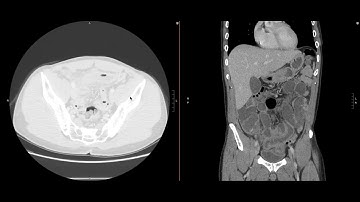

Abdominal Imaging Call Prep Cases: Acute Uncomplicated Appendicitis (CT) Case 3 Discussion